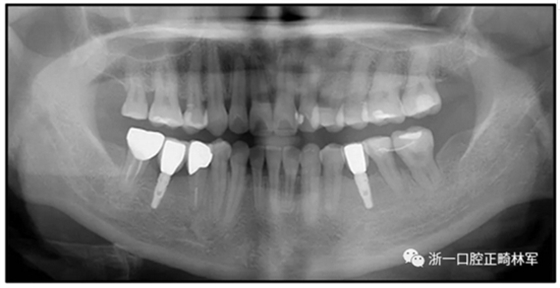

36歲;女性;尋求下頜左后方區(qū)域間隙管理的建議(圖1和圖2),通過治療獲得了良好的牙頜面效果(圖3和圖4)。她被診斷患有骨性I類和代償性牙性II類錯合畸形,并且上頜左側尖牙缺失(圖1和2)。大約七年前,由于不可修復的齲齒,拔除了下頜左側第一和第二磨牙(圖5)。37相鄰的第三磨牙向近中移動并傾斜入間隙,導致無牙頜間隙減小至約14 mm(圖2和圖5)。臨床和影像學評估顯示多發(fā)性齲損和在下頜右側567處有一不良的固定橋修復體(圖1和5)。此外,下頜左中切牙缺失,造成下頜中線向左側偏移約3 mm(圖1和圖2)?;颊咦栽V,她的右上第一前磨牙和左上尖牙在13歲時由其家庭牙醫(yī)拔除,因為它們被阻塞到頰側萌出(圖1)。上頜第二磨牙缺失(未知病因),并且相鄰的第三磨牙已經(jīng)轉移到第二磨牙間隙中。如補充材料所示,美國正畸學差異指數(shù)DI是28分。種植體部位(下頜左側和右側第一磨牙)由于復雜性得到額外4分(補充材料)。

圖5. 治療前的側位片(上圖)和全景(下圖)的X光片

治療選擇

修復下頜左側缺牙區(qū)的第一種方法是增加牙槽嵴骨量并植入2顆種植體。然而,這樣就要增加一個植體,且手術難度大,效果難以預測,因為缺牙區(qū)的牙槽骨嚴重不足。此外,因為左側下頜第三磨牙的近中傾斜(圖5),第三磨牙與種植體之間易形成食物嵌塞和牙菌斑積聚,有引起長期的牙周問題,如牙周炎或種植體周圍炎的風險。第二種選擇是用可摘局部義齒替代缺失的下頜骨左側磨牙,但第三磨牙的近中傾斜可能會影響義齒的就位道。解決這個問題,需要拔除第三磨牙或進行修復,使磨牙有一個符合標準的牙冠?;颊哂捎陬~外的外科手術,原第三磨牙無法完全發(fā)揮功能,牙周風險加劇,拒絕了這兩種可選擇的治療方法。